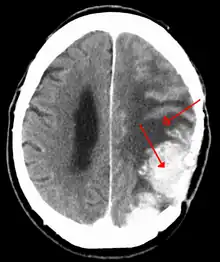

A contrast-enhanced CT scan of the brain, demonstrating the appearance of a meningioma

Meningiomas are visualized readily with contrast CT, MRI with gadolinium,[22] and arteriography, all attributed to the fact that meningiomas are extra-axial and vascularized. CSF protein levels are usually found to be elevated when lumbar puncture is used to obtain spinal fluid. On T1-weighted contrast-enhanced MRI, they may show a typical dural tail sign absent in some rare forms of meningiomas.[17]